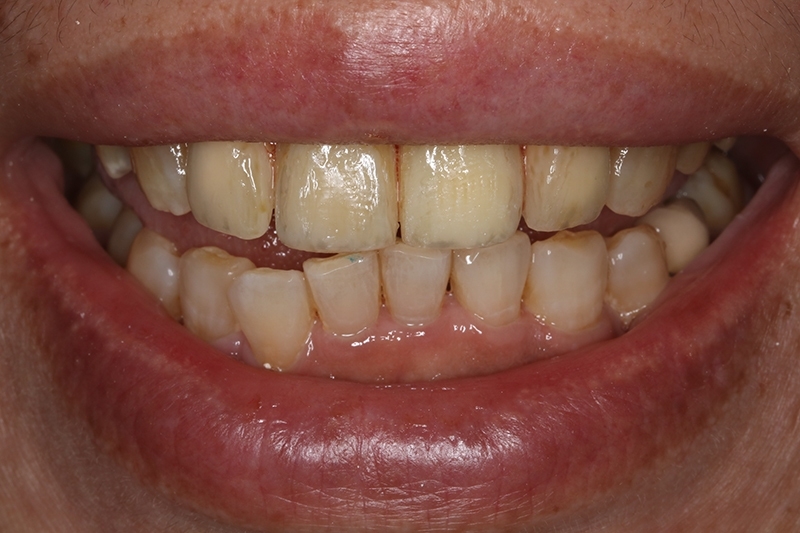

臨時假牙微笑照

門牙植牙全瓷冠+側門牙全瓷冠完成照